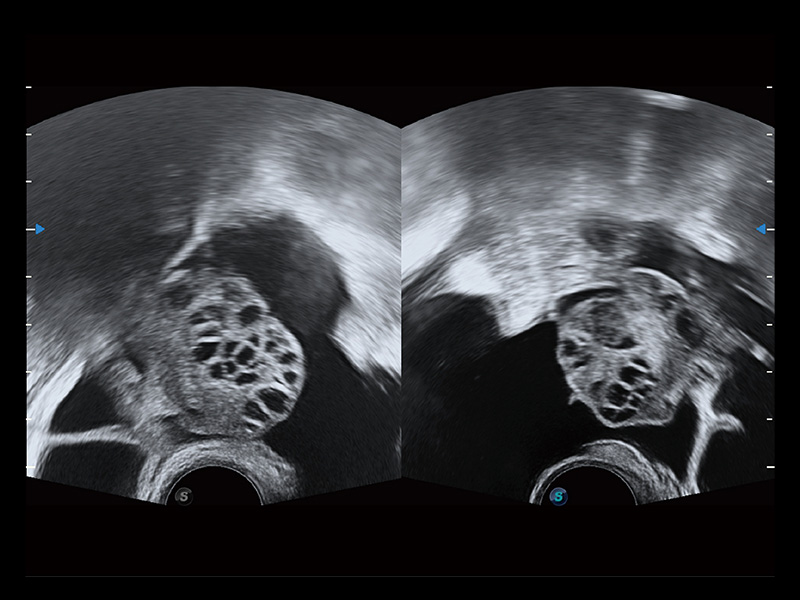

卵巢多囊样改变

曲柄设计方便术者与操作者配合工作。220°大角度扫查配备专用的穿刺架,可清晰显示穿刺针进针过程,保障取卵操作精准与安全。

大视野角度下观察使医生无需转动探头即可有效观察各方位病变,减小病人痛苦,可进行女性生殖系统检查及试管婴儿的临床研究。